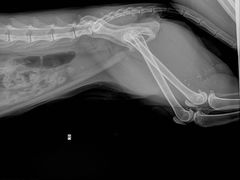

大圆_2963 | 25-08-11

报错

• -拜鲁耶动物诊疗中心·宠家动物医院